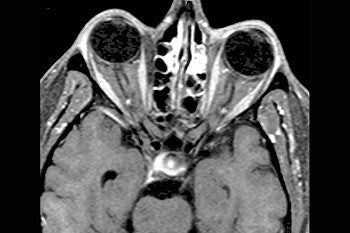

Axial (top) and coronal (below) contrast-enhanced, fat-suppressed T1-weighted images through the orbits demonstrate diffuse homogeneous thickening of the medial, lateral, and inferior rectus muscles of the right orbit. There is minimal thickening of the superior muscle group. The tendinous insertions are not involved. There are also scattered inflammatory changes in the ethmoid sinuses and the left maxillary sinus.![]() |

The patient underwent MR imaging on a 1.5-tesla Signa scanner (GE Medical Systems, Waukesha, WI). Gadolinium-enhanced, fat-suppressed, T1-weighted images were obtained through the orbits. Contiguous images of 4 mm with a 1-mm interslice gap in the axial and coronal planes were obtained, Som told AuntMinnie.com.

Prior to treatment, the MR scans showed "diffuse homogenous thickening of the medial, lateral, and inferior rectus muscles of the right orbit." In addition, scattered inflammatory changes in the ethmoid sinuses and left maxillary sinus were seen, the group reported.